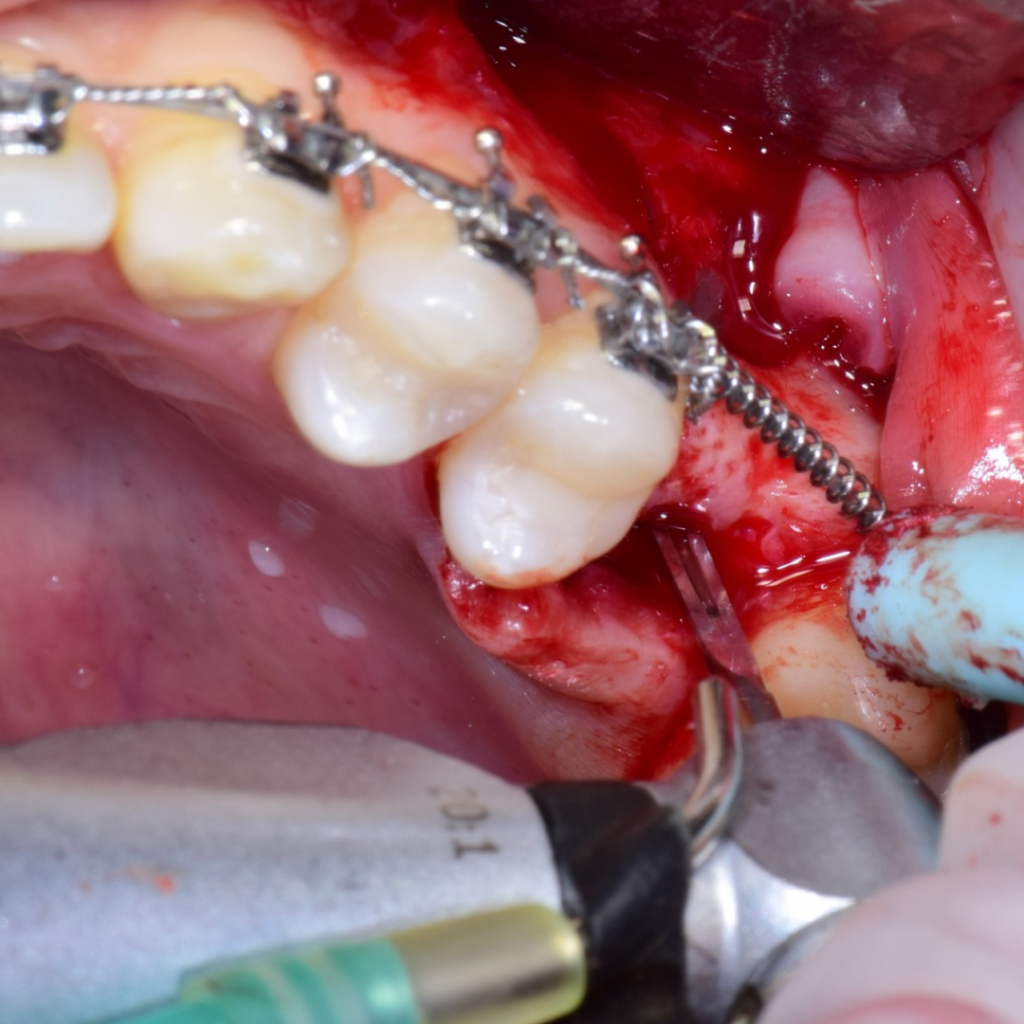

По результатам диагностики принято решение провести синус-лифтинг с помощью боров SinPro. В ходе вмешательства установлены имплантаты AnyRidge и AnyOne с первичной стабилизацией 40 Ncm.